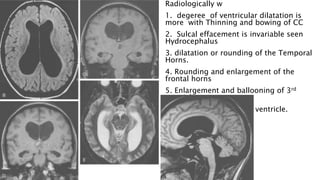

Radiologically w

1. degeree of ventricular dilatation is

more with Thinning and bowing of CC

2. Sulcal effacement is invariable seen

Hydrocephalus

3. dilatation or rounding of the Temporal

Horns.

4. Rounding and enlargement of the

frontal horns

5. Enlargement and ballooning of 3rd

ventricle

6. Enlargement of fourth ventricle.